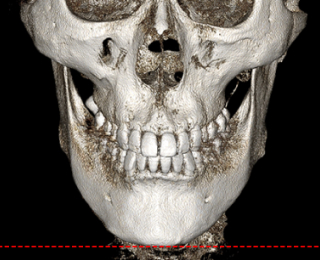

• 신경 보존 절골법 이미지

무분별한 절골은 감각 이상과 같은

심각한 후유증을 남길 수 있습니다

신경 손상을 최소화하여

안전을 최우선으로 합니다

수술 전 3D-CT를 통해 신경의 위치를

1mm까지 분석하고,

원장님이 직접 수술 경로를 디자인하여

신경 손상을 원천 차단합니다

* 수술전 원장님이 직접 디자인한 사진입니다